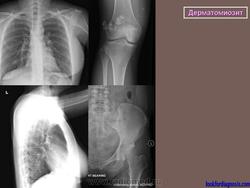

Изменения в легких, обусловленные самим заболеванием, относительно редки. К ним относят интерстициальный фиброз, иногда с развитием хронического легочного сердца. Аспирация слюны и пищи и гиповентиляция легких предрасполагают к развитию банальной инфекции.

3) висцерально-мышечный синдром: поражение дыхательных мышц, включая диафрагму (одышка, высокое стояние и вялость дыхательных экскурсий диафрагмы, снижение жизненной емкости легких); мышц глотки, пищевода, гортани (дисфагия с поперхиванием, дисфония), миокарда (миокардит, дистрофия, интерстициальный отек);

Британский журнал радиологии (2005)

http://radiographics.rsna.org/content/31/6/1651.full

https://radiopaedia.org/articles/dermatomyositis

Дифференциальная диагностика изображения